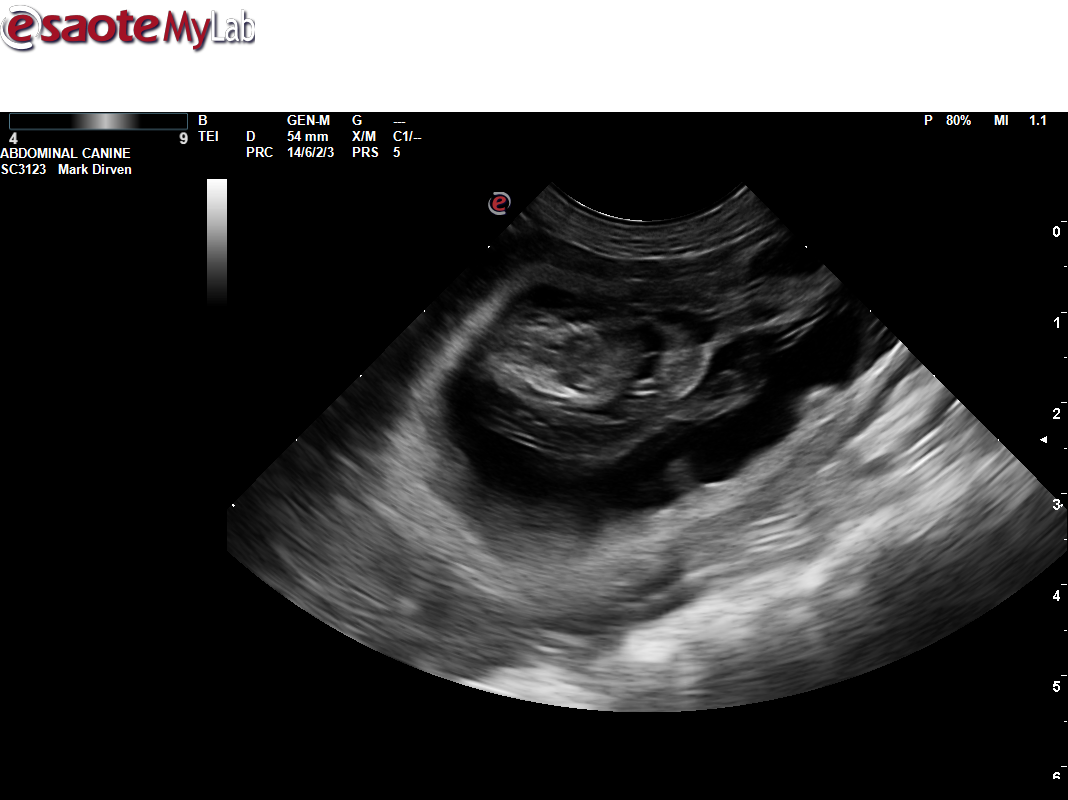

Uitslag heupen Mayla

Mayla 4 september 2019 heupen HD A